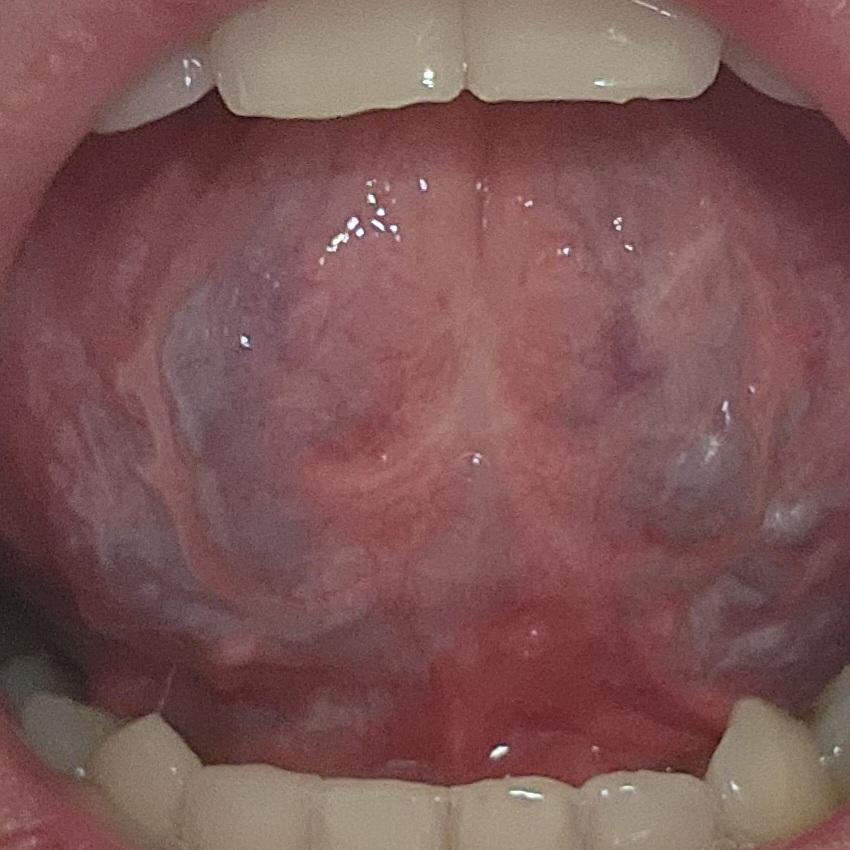

혀 밑부분이 검은색인데 괜찮가요?

혀 밑에 부분이 거울을 보니깐 검은색 가까워 보이는데 괜찮은건가요?

안괜찮다면 어디 병원을 가야 하는지 알려주실수 있으신가요?

올려주신 사진 속 검푸르스름한 색은 정맥혈로 인한 색깔로 이상소견은 아닙니다. 걱정하지 않으셔도 되겠습니다.